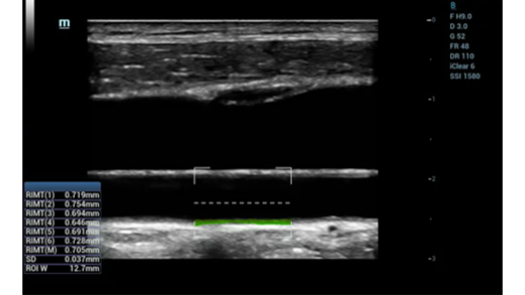

Dedicated and professional solutions